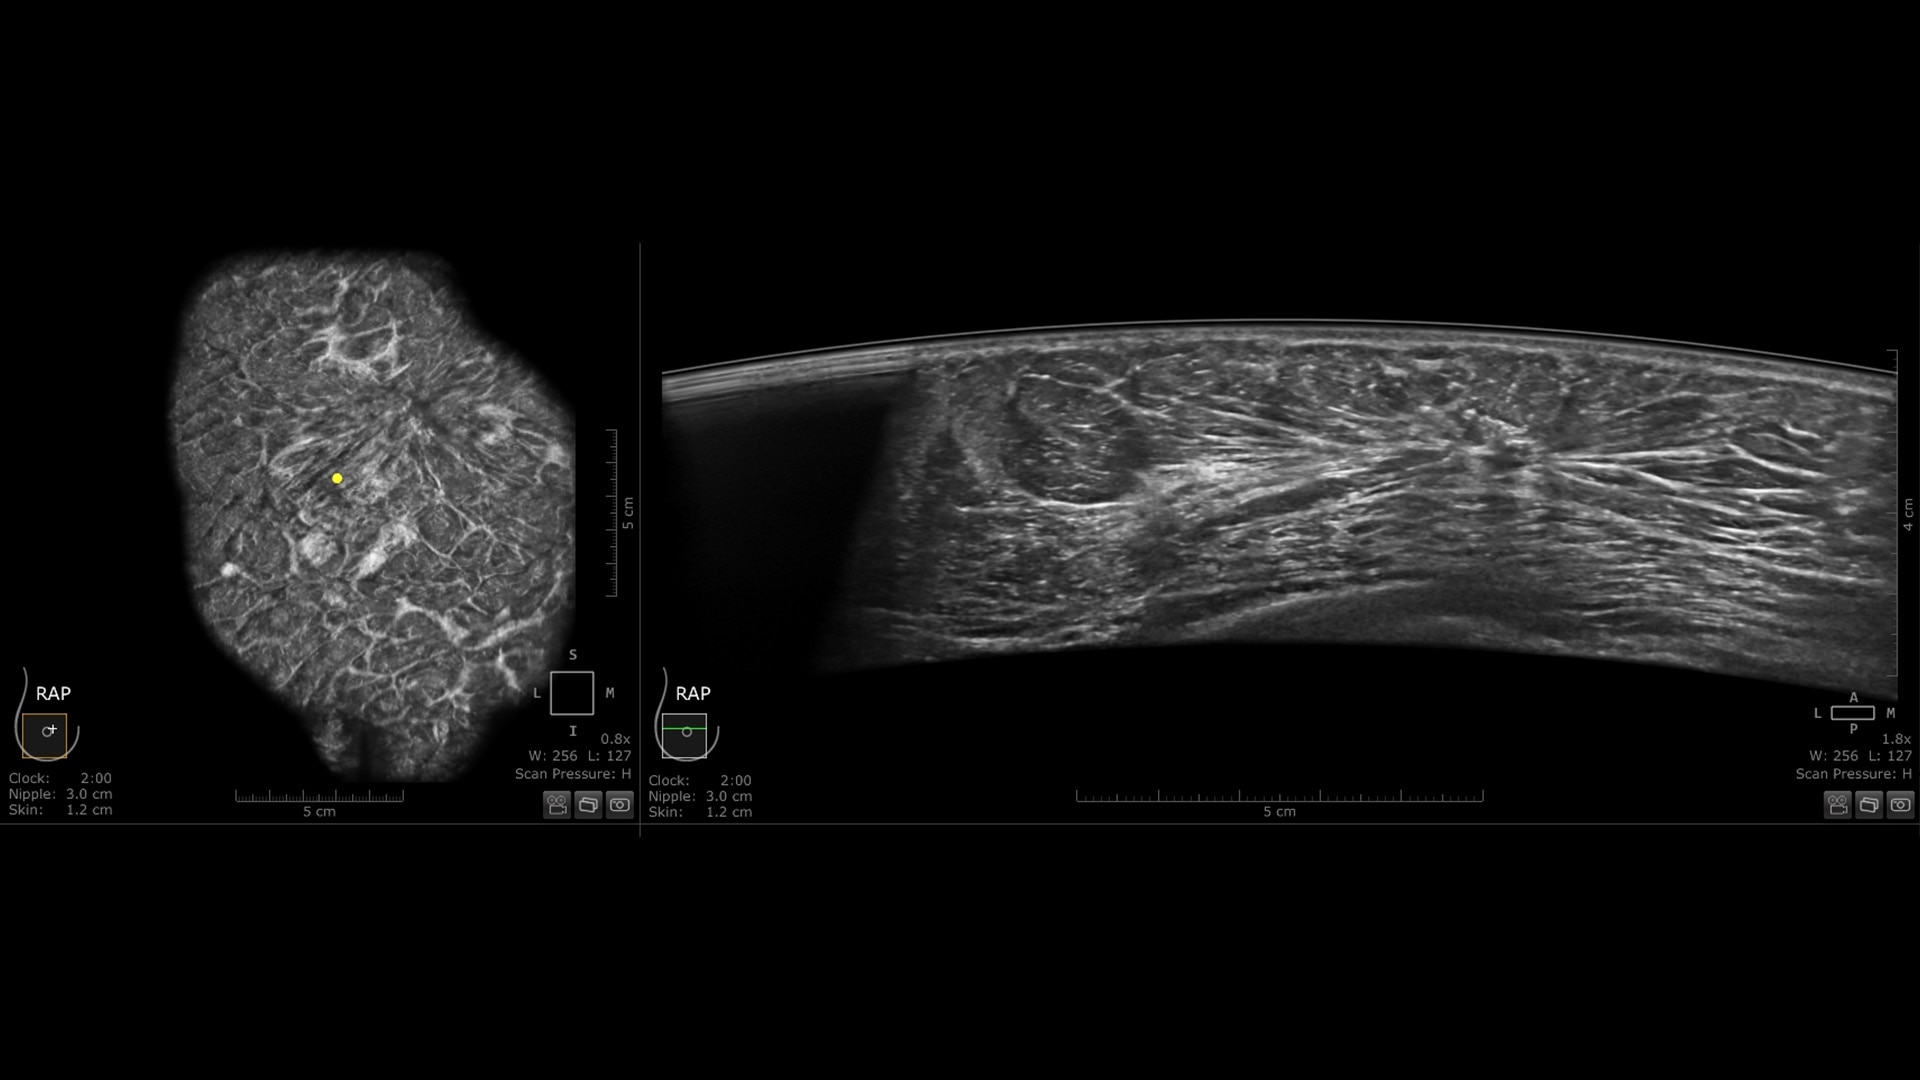

The Invenia ABUS Premium is designed for high patient throughput and extraordinary image quality to provide a great level of confidence. With its innovative design, it’s easy to use, reproducible, user-independent, standardized and allows reading anywhere.

The novel Reverse Curve™ transducer is designed for enhanced performance

Its gentle 15.3 cm shape follows the breast's natural contour, enhancing patient comfort* and ensuring full contact for comprehensive coverage. The improved image quality* increases diagnostic confidence for reading ABUS exams.

Excellent image quality and 40% faster scan speed

• cSound Imageformer, software-based processing, produces exquisite, reproducible images by leveraging automatic focus at every pixel.

• Fast Scan increases scan speed by 40%*, fostering improved efficiency and patient throughput.